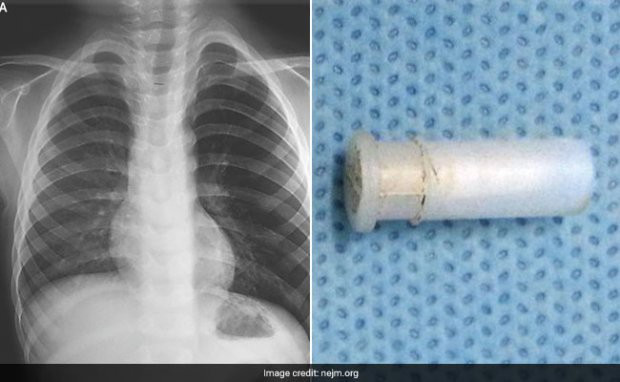

| Hình ảnh chụp phổi cậu bé và dị vật. |

Cha mẹ cậu bé cho biết, cậu bé đã đùa nghịch với một cái còi đồ chơi trước khi bắt đầu ho liên tục kèm theo những tiếng rít như tiếng huýt sáo. Các bác sĩ chụp X-quang vùng ngực của cậu bé, phát hiện thấy phổi trái của cậu bé bị hyperinflated (hiện tượng phổi căng phồng quá mức), lý do là do một vật cản đã chặn đường dẫn khí vào phổi, gây tắc đường hô hấp.

Cuối cùng, các bác sĩ sử dụng ống soi phế quản, loại bỏ được vật thể là một cái còi đồ chơi ra ngoài qua đường họng cậu bé.